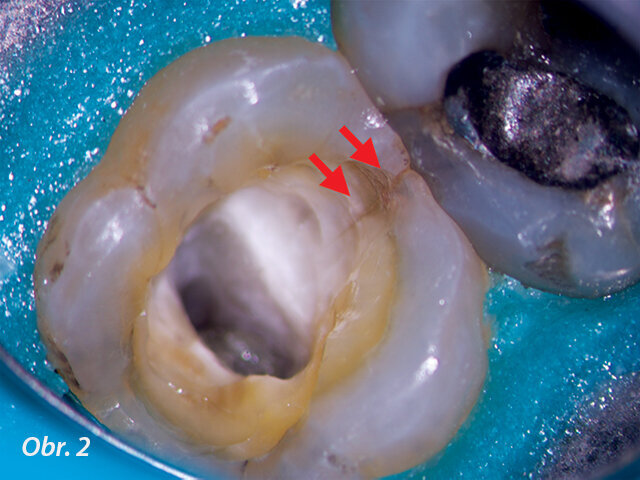

Vyhodnocení rozsahu meziální lomové linie (šipky) u levého druhého horního moláru. Mikroskopické vyšetření potvrdilo nutnost rekonstrukce.

Pro endodontistu je dentální mikroskop užitečný při určování diagnózy a klinických procedurách. Mikroskop může být diagnostickou pomůckou při hledání kazu, nevyhovujících korunek nebo okrajů výplně (obr. 1), nebo při posuzování prasklin či lomových linií. Během ošetření kořenových kanálků pomáhá zvětšení a osvětlení zajištěné operačním mikroskopem s odstraněním kazu, při preparaci přístupu, odstraňování kalcifikací z dřeňové dutiny, nalezení ústí kořenových kanálků, prasklin a lomových linií (obr. 2) a při ošetření vnitřních resorpcí. Pod mikroskopem jsou i minimální změny v barvě dentinu a textuře výrazné, například vývojové linie na dně dřeňové dutiny dovedou lékaře k ústí kořenových kanálků nebo tmavší barva dna dřeňové dutiny umožňuje lékaři sama o sobě bezpečnější odstranění dentinu.